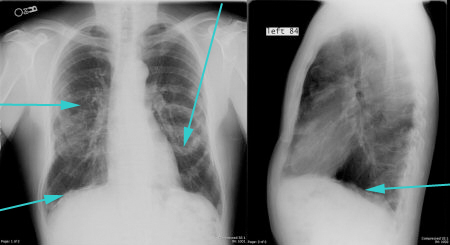

- рентген легких в двух проекциях: фронтальной и боковой;

При перкуссии отмечается ослабление перкуторного звука, причем верхняя граница представляет собой косую линию-Дамуазо, которая хороша видна на рентгенографии. При выслушивании легких фонендоскопом отчетливо слышен шум трения плевры, он похож на скрип снега. Дыхание в местах скопления жидкости резко ослаблено.

На рентгенографии симптомы выпотного плеврита легких отображаются как интенсивное однородное затемнение в нижних долях органа. Высокое стояние диафрагмы наблюдается при небольшом скоплении жидкости. Средостение смещено к здоровому легкому. При выполнении снимка в латеропозиции (больной ложится на бок) происходит горизонтальное смещение экссудата.